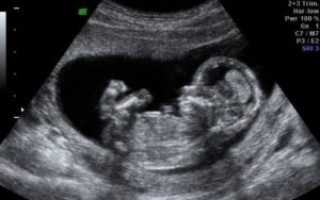

Узи на 12 неделе беременности. Мальчик. УЗД -12 недель.Узи на 12 неделе беременности. Мальчик. УЗД -12 недель.

Ультразвуковое изображение плода в 11 недель

При первом ультразвуковом исследовании определяется срок гестации. Под этим термином понимается возраст эмбриона с момента оплодотворения. Расчет срока осуществляется с учетом копчико-теменного размера (сокращенное обозначение – КТР) плода. Прослеживается следующая закономерность:

• КТР у будущего ребенка составляет 10 мм – это в среднем 7 недель;

• КТР равно 30 мм – это примерно 9 недель и 5 дней;

• КТР равно 60 мм – это около 12 недель и 3 дней.

По поводу КТР стоит отметить, что на 11−12-й неделях допустимые нормы этого показателя – от 34 до 50 мм. Заметное отставание показателя от нормативных значений – прогностически неблагоприятный признак. Он может свидетельствовать о неразвивающейся беременности, задержке или аномалиях развития плода.

Обязательно при первом сканировании оценивается сердечная деятельность будущего ребенка. Сердцебиение начинает визуализироваться при копчико-теменном размере 5 мм и более.

Когда оно отсутствует при КТР 5−8 мм, специалисты назначают повторное исследование через неделю для оценки жизнеспособности плода.

В ходе ультразвукового исследования производится расчет толщины воротникового пространства (или кожной шейной складки) у будущего ребенка − ТВП. На 8−12-й неделях значение не должно быть больше 2,5 мм.

При утолщении складки есть вероятность наличия у плода хромосомных патологий. Например, патологический размер может указывать на синдром Дауна.